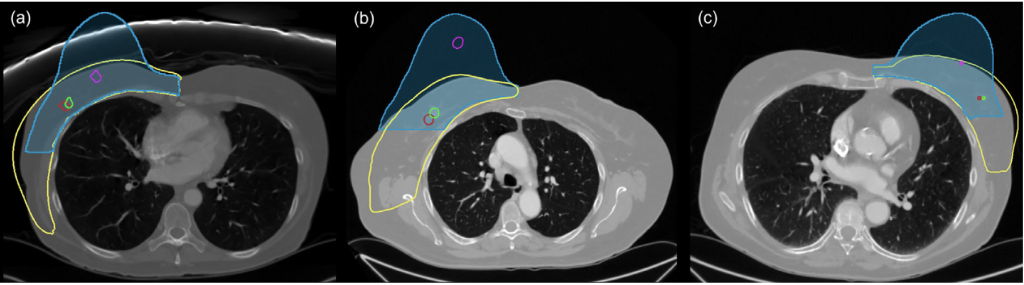

- Cáncer: propagación y simulación pre-operatoria

- Alfano, F., Navas, P., et al. (2025) Simulation of the Effect of Gravity for Breast Surgical Planning: Feasibility of a Visco-hyperelastic Mechanical Model. Bioengineering & Translational Medicine, DOI: 10.1002/btm2.70044